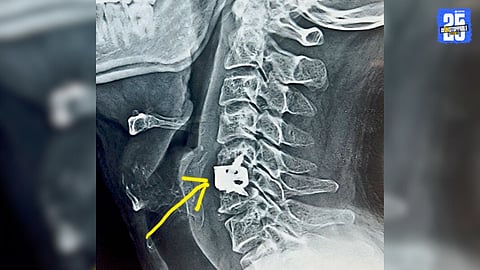

When Neck Pain Radiates to Arm and Fingers

मान, दंड आणि हातात जाणाऱ्या असह्य वेदनांमागे ‘सर्व्हायकल रॅडिक्युलोपथी’ हा नसेचा गंभीर आजार कारणीभूत असू शकतो. योग्य वेळी एमआरआय तपासणी आणि तज्ज्ञ शस्त्रक्रियेमुळे रुग्णाला वेदनामुक्त जीवन मिळू शकते.

तीव्र वेदनेमुळे नेहा भल्ला अक्षरशः हतबल झाल्या होत्या. वेदनेने विव्हळणं म्हणजे काय, हे त्यांच्याकडे बघून आजूबाजूच्यांना स्पष्ट जाणवत होते. अनेकदा आपण ‘तडफडणे’ वगैरे शब्द अतिशयोक्ती म्हणून वापरतो; पण त्या दिवशी त्यांच्या त्रासासमोर ते शब्दही तोकडे पडत होते. गेल्या तीन महिन्यांपासून त्यांची मान पूर्णपणे आखडली होती. त्यांच्या भाषेत सांगायचे, तर मान ‘लॉक’ झाली होती.